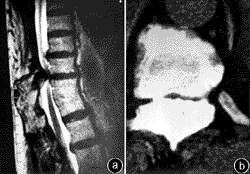

(5)MRI檢查:具有更大的優越性既可對矢狀面進行大範圍觀察又便於發現病變及排除椎管內可能存在的其他疾患。但對骨化的韌帶橫斷面顯示欠佳且對早期較小或偏側性病變容易漏診。

綜上所述,就診斷準確率而言MRI與CT(或CTM)二者的結合是診斷本病的最佳選擇。

4.MRI檢查 主要用於觀察骨化的黃韌帶與脊髓的關係一般列為常規檢查尤其是擬行手術的病例(圖1)。